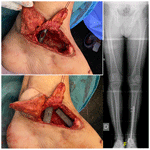

https://jbji.copernicus.org/articles/10/419/2025/jbji-10-419-2025-f01

Figure 1Intraoperative images. In this composed image, the following are presented: the arthrodesis nail (a), tantalum spacers in the void left by the talus (b), the remaining void filled with CERAMENT® (c), and the autograft and closure of the Masquelet membrane (d).

In August 2019, the patient suffered an open dislocation of the talus without fracture. It was reduced and fixed with 2 K-wires. One week later, he underwent reoperation due to purulent discharge; the infection was not controlled and skin necrosis appeared. A fasciocutaneous anterolateral free flap of the thigh associated with a new debridement was performed 1 month later.

In November 2019, the infection relapsed; at this point, he was referred to our hospital. The flap was in a good condition, with some erythema around it. MRI confirmed AVN and FRI with no other bones involved or purulent collections (Fig. 2).

https://jbji.copernicus.org/articles/10/419/2025/jbji-10-419-2025-f02

Figure 2MRI images of the preoperative state of the talus. Sagittal MRI images showing signs of avascular necrosis and osteomyelitis: (a) T1 and (b) STIR images.